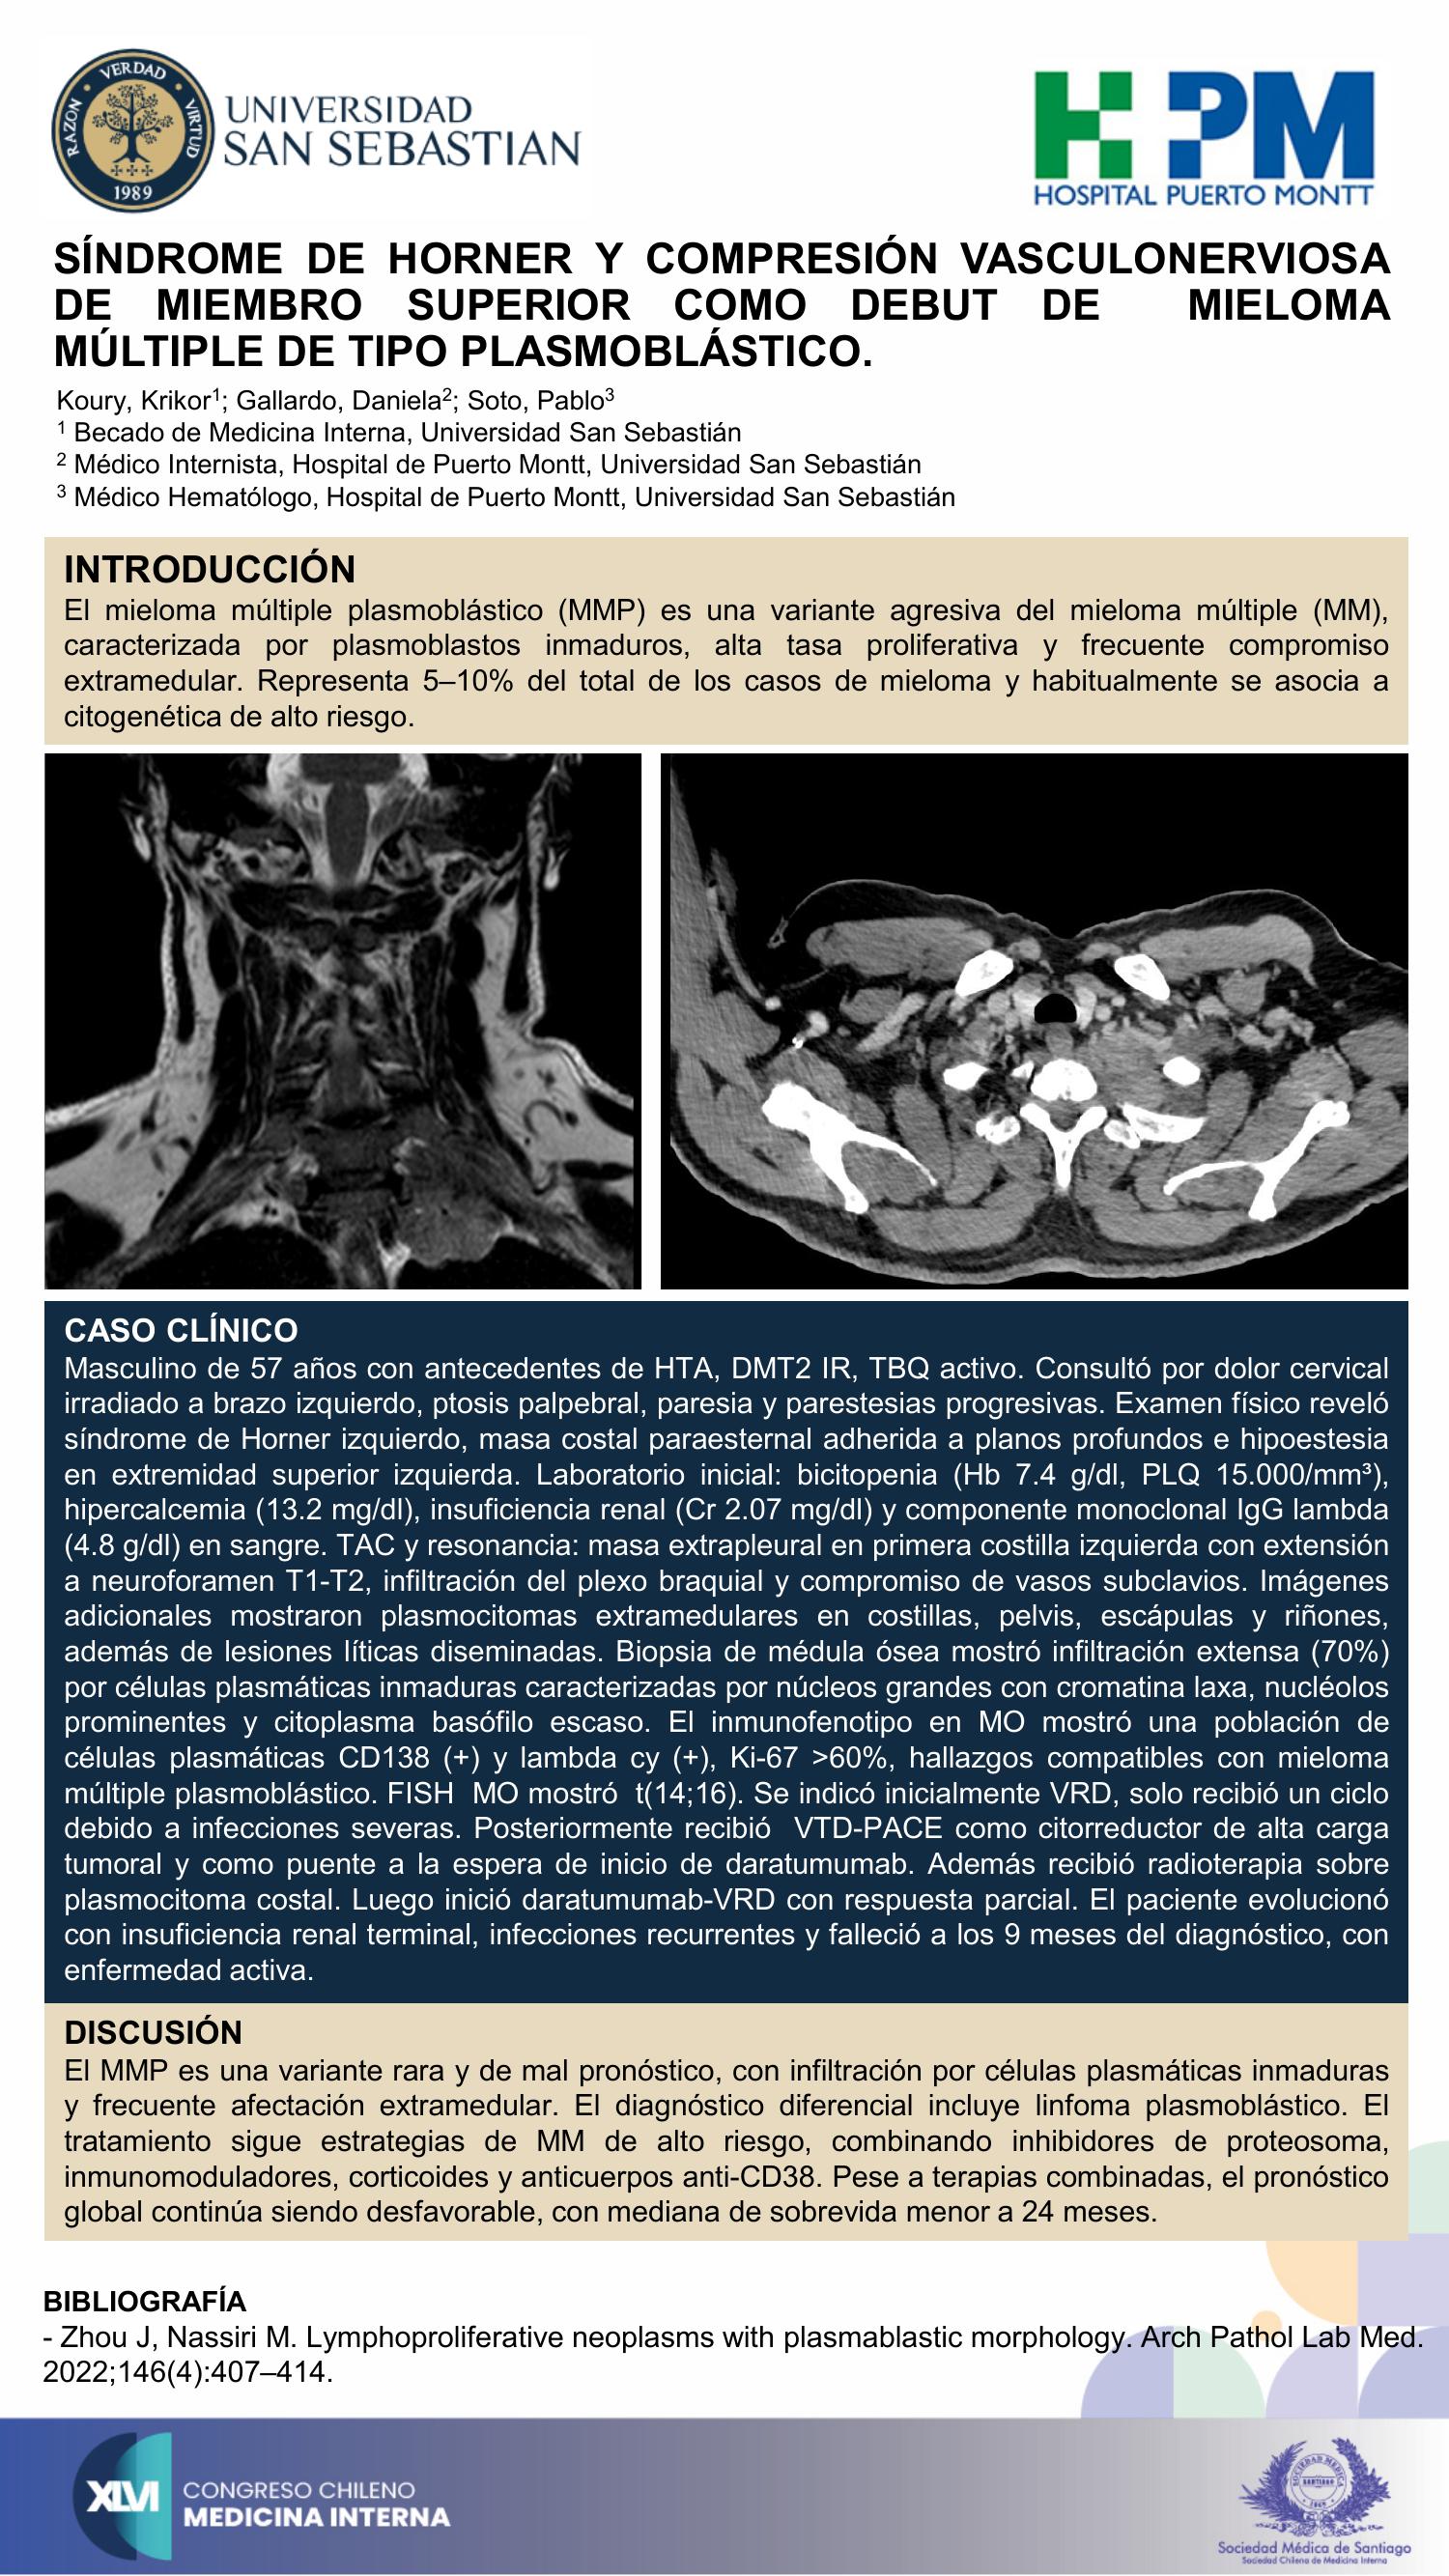

SÍNDROME DE HORNER Y COMPRESIÓN VASCULONERVIOSA DE MIEMBRO SUPERIOR COMO DEBUT DE MIELOMA MÚLTIPLE DE TIPO PLASMOBLÁSTICO. A PROPÓSITO DE UN CASO.

Krikor Koury Kachichián, Daniela Gallardo Andrade, Pablo Soto Vargas

Tótem 6, 11-09-2025, 13:29 - 13:36